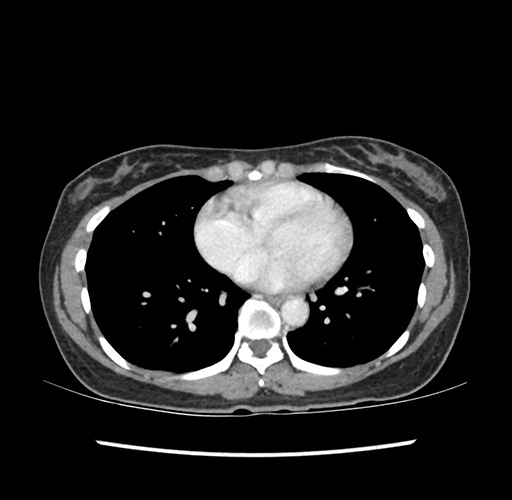

Imaging Analysis

Look through the patient's CT scan to identify any areas of concern for the necessary procedure.

Based on your CT findings, which issue(s) would give reason for "planned slowing down moment(s)" in this case?